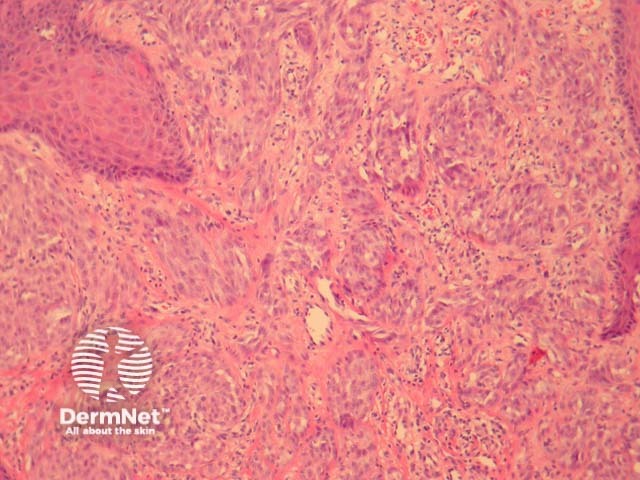

It has recently been shown that spitzoid neoplasms harbour kinase fusions of ROS1 (17%), NTRK1 (16%), ALK (10%), BRAF (5%) and RET (3%) in a mutually exclusive pattern. These mutations appear to be present in a subset of both benign and malignant Spitzoid tumours. ALK-mutated Spitz tumours are often compound melanocytic proliferations with a predominant intradermal growth. These lesions often have a plexiform dermal growth of intersecting fascicles of fusiform melanocytes (figures 11, 12, 13). ALK immunohistochemistry can confirm this fusion (figure 14). Some of these mutations may provide therapeutic targets for malignant tumours.

Figure 11

Figure 12

Figure 13